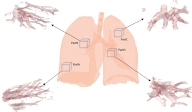

The CT image of lung is from DIR-LAB [9] that provides a group of 4D CT images of lung consist of 10 cases, each one having a thoracic with six phases. As shown in Figure 2, we evaluate the validity of our method using four parts (PartA, PartB, PartC, PartD) segmented from the data at time 0 of first case (Case1_T00). Among the four parts of data, PartA and PartC are located at the edge of lung with small blood vessels, and PartB and PartD are located at the central of lung with large blood vessels, all of which are chose to demonstrate the effectiveness for different size of blood vessels.

Figure 2: A comparison between bifurcation detection methods. View Figure 2

In the second experiment, the information of four parts data (show in Figure 2) is listed in Table 1. Figure 6, Figure 7, Figure 8 and Figure 9 show the results of bifurcation detection of three methods on the four parts of lung, which include 3D views (detected bifurcations are marked by yellow ball) and 2D views (bifurcation locations are marked by red x). Table 2, Table 3, Table 4 and Table 5 are the statistics on the number of detected bifurcations of three methods.